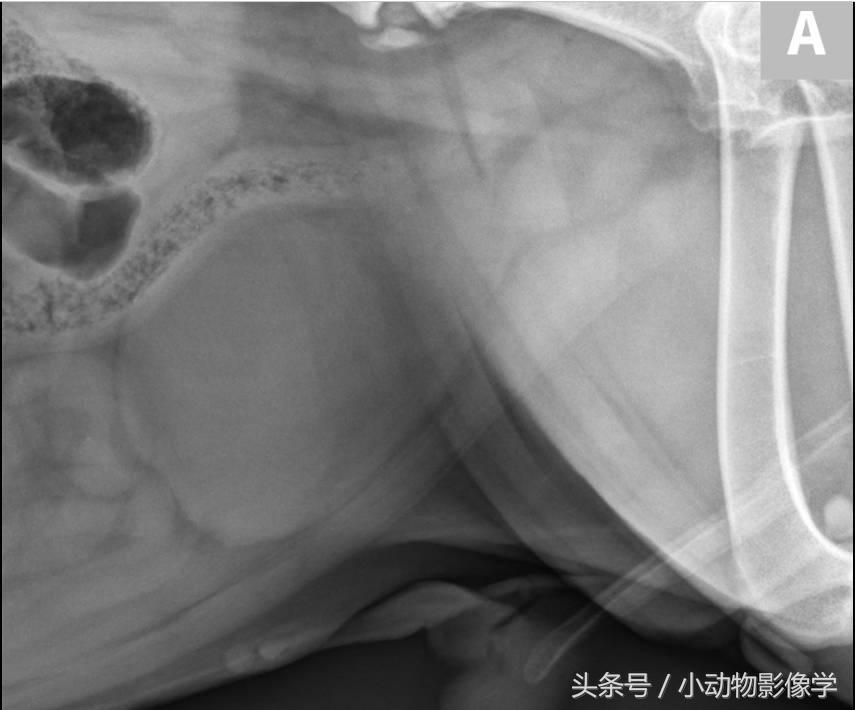

图7A、一只猫的腹部侧位平片,腹膜后隙的腹侧方向(箭头)有多个小型椭圆不透明矿物阴影叠加。这些线性排列的不透明矿物质从肾的尾部延伸到膀胱。

图7B、图7A中猫的超声图像,可见X光片上的结石(箭头)都分布于左输尿管内(三角箭头之间)。

图7C、同一只猫的顺行性超声引导肾盂造影影像,可见中度肾积水(H)和输尿管内多处充盈缺损(结石)(箭头)。尽管输尿管结石数量很多,但动物输尿管仍只是部分梗阻,因为阳性造影剂在结石远端(三角箭头)。